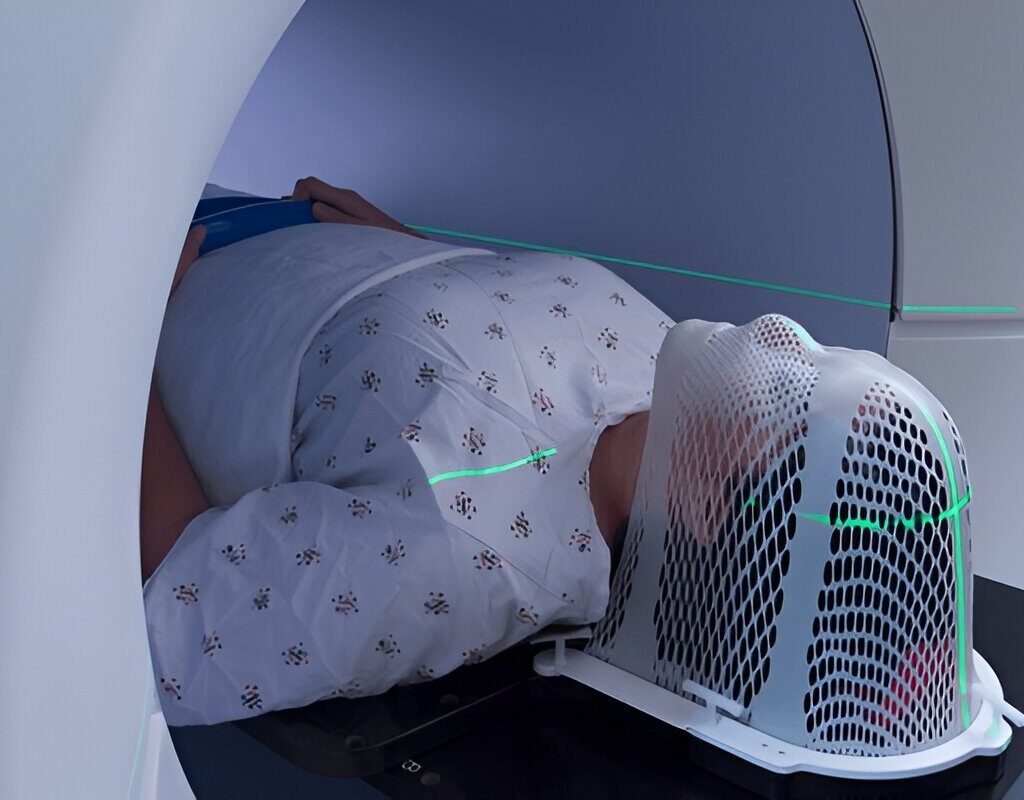

- Radiation Therapy:

High-energy rays to destroy cancer cells.

Our ENT treatment guidelines align with NCCN (National Comprehensive Cancer Network) and head and neck cancer treatment guidelines NSSN, ensuring standardized, evidence-based care.